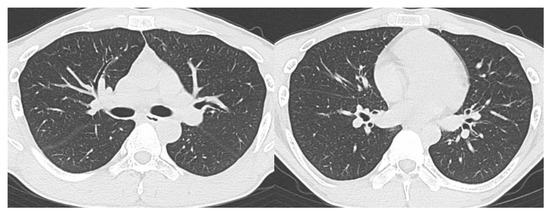

- CO-RADS 2 means a low level of suspicion for pulmonary lesion resulting from COVID-19, based on CT findings in the lungs typical of etiology indicative of infections other than COVID-19, including bronchitis, infectious bronchiolitis, bronchopneumonia, lobar pneumonia, and pulmonary abscess. Findings include a tree-in-bud sign, a centrilobular nodular pattern, lobar or segmental consolidation, and lung cavitation.